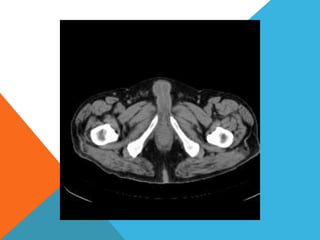

El paciente presentó síntomas de sangrado digestivo y pérdida de peso. Exámenes revelaron gastritis crónica asociada a H. pylori. Un tumor fue descubierto en una colonoscopia normal. La cirugía removió un tumor fibroide solitario, una rara neoplasia mesenquimal que usualmente crece lento y tiene bajo potencial de malignidad. El pronóstico después de la remoción quirúrgica es generalmente bueno.